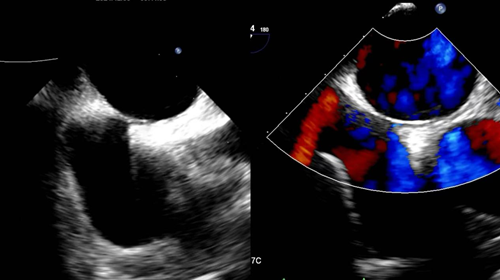

4.心脏瓣膜病:如瓣膜狭窄、关闭不全、脱垂等。

(经食管超声显示二尖瓣反流)

5.感染性心内膜炎,如有无赘生物形成、穿孔、腱索断裂、瓣周脓肿等。

6.心脏瓣膜置换术后,TEE超声图像优于TTE,可对人工瓣膜功能结构及功能准确评价,如有无人工瓣膜的狭窄、卡瓣、瓣周漏、感染性病变、血栓、血管翳等并发症。